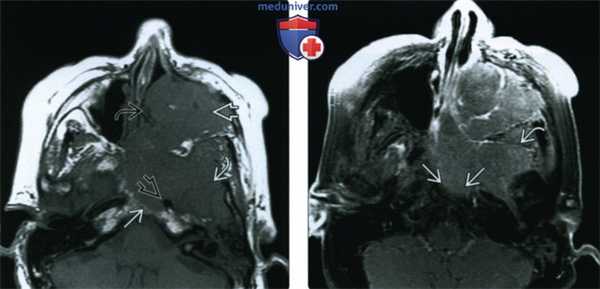

(Слева) При аксиальной МРТ Т1 определяется ПКР полости носа с вовлечением носовой перегородки, распространением кнаружи в крылонебную ямку и кзади в носоглотку, к основанию черепа.

(Справа) При аксиальной МРТ Т2 FS визуализируются края опухоли, отличной от утолщенной слизистой оболочки верхнечелюстной пазухи, превертебральных мышц и костного мозга ската с подавленным сигналом. Утолщение слизистой оболочки сосцевидного отростка связано с обструкцией евстахиевой трубы.